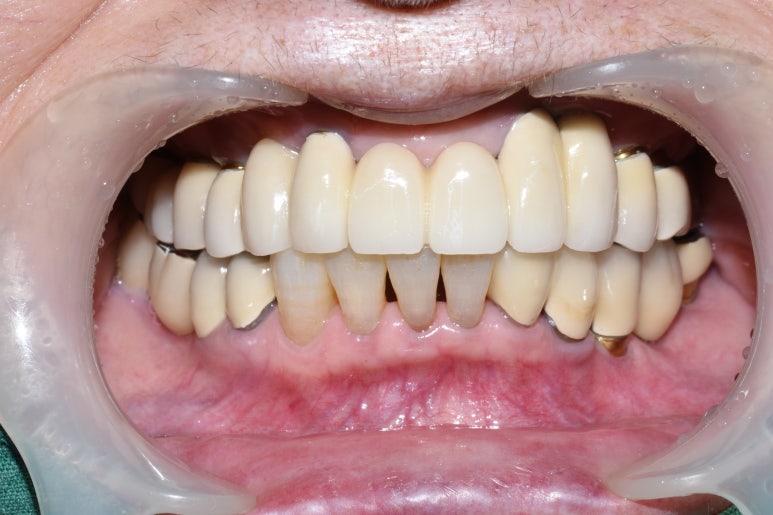

- 상악 전체임플란트, 하악어금니 없는 부분 임플란트

상악 흔들리는 브릿지와 치아 발치 후 상악전체 임플란트

상악 전체 임플란트 후

- 상악 전체임플란트 및 하악 어금니 없는 부위 임플란트